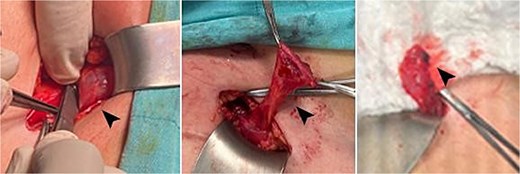

A right inguinal exploration was performed under general anesthesia. A cystic structure consistent with a canal of Nuck cyst was identified within the inguinal canal (Fig. 2). Dissection was performed around the cyst until it was completely released. The cyst was excised in its entirety and sent for histopathological analysis that confirmed the diagnosis of a benign cyst lined with mesothelial cells and containing serous fluid, consistent with a canal of Nuck cyst (Fig. 3). Postoperatively, the patient recovered well, tolerated her diet, ambulated independently, and maintained clean dressings.

Intraoperative images showing the cyst, highlighted by the head arrow.